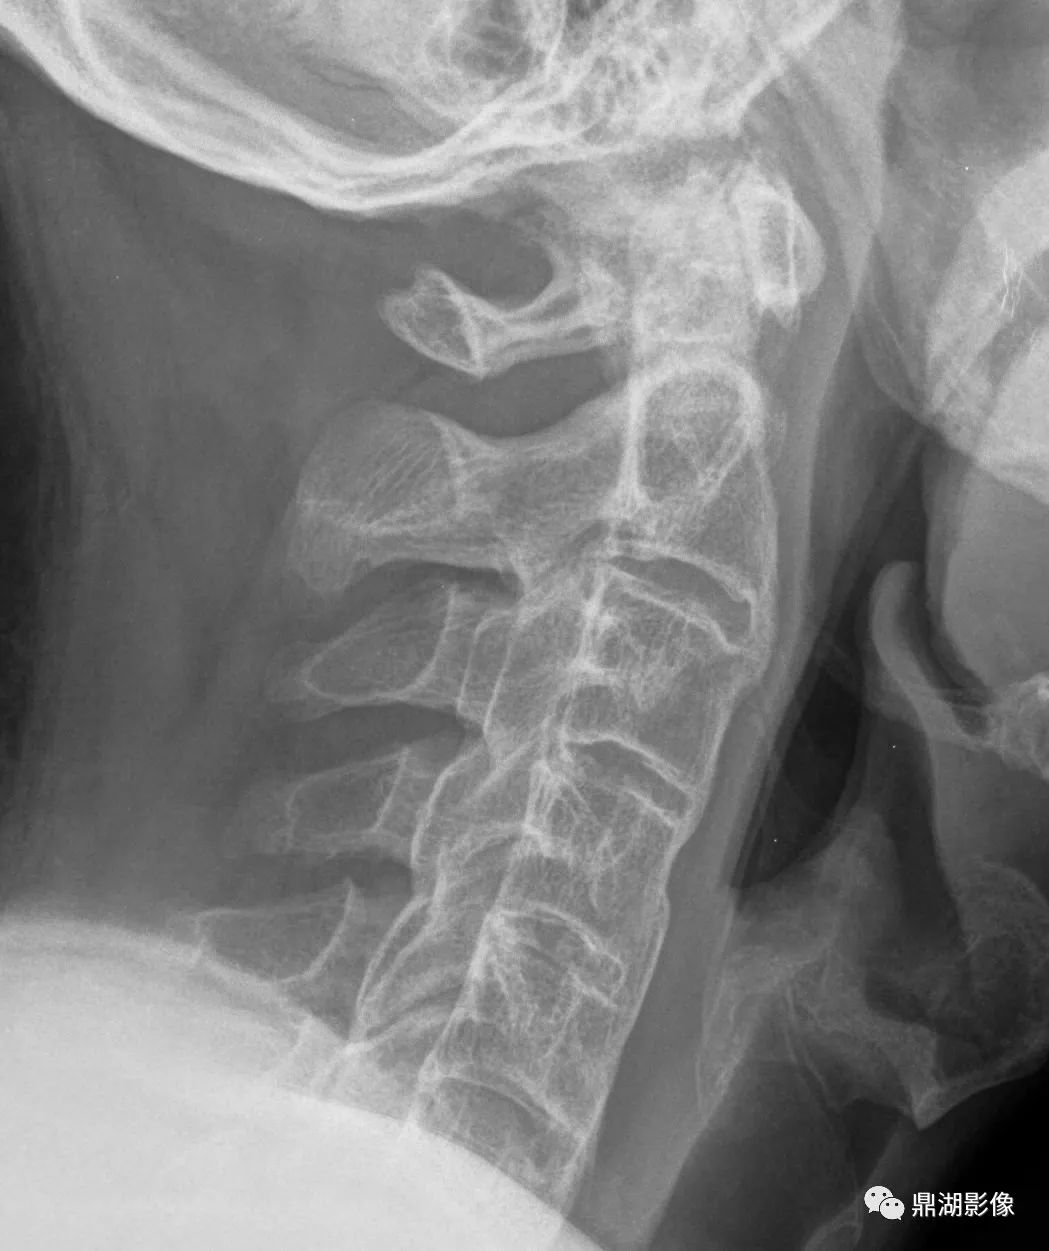

- 脊柱最常受累

- 胸椎最常见,其次为颈椎、腰椎

- 椎体前外侧连续性骨化,后纵韧带、黄韧带也可受累非边缘性韧带骨赘,即骨化不发生于间盘边缘,形成波浪样外观

- 随时间进展骨化厚度可从1-2mm增至20mm

- 椎间隙高度正常